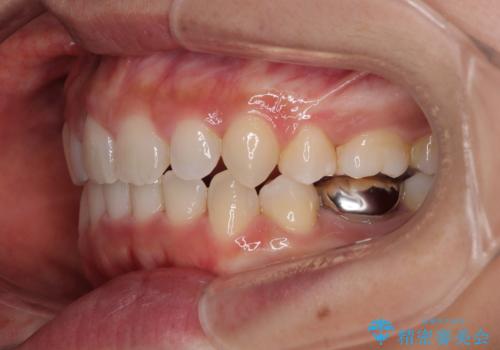

途中出産や育児があり、治療期間長くなってしまいましたが、ストレスなく唇が閉じられるような口元に仕上げることができました。